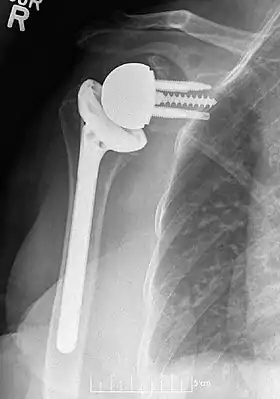

![]() Plain film radiograph in anteroposterior (AP) view of a right shoulder status post reverse shoulder arthroplasty using a prosthesis with a lateralized center of rotation. | |

Modern reverse shoulder implants consist of multiple parts. On the scapula bone, there is a metallic baseplate that grows into the bone of the native glenoid, screws and/or pegs that hold this in place, and a round metallic “glenosphere” component that is mated to the baseplate via several different mechanisms. On the humerus bone, there is typically a concave polyethylene liner that articulates with the convex glenosphere and is attached to a humeral stem that grows into the native humerus or is cemented into place. Within this basic structure there are multiple different variations of implants, and to date there is no consensus on which design is superior, although several studies have demonstrated some benefits to certain combinations.[9][10][11] One such modern reverse shoulder implant system is the AltiVate Reverse.